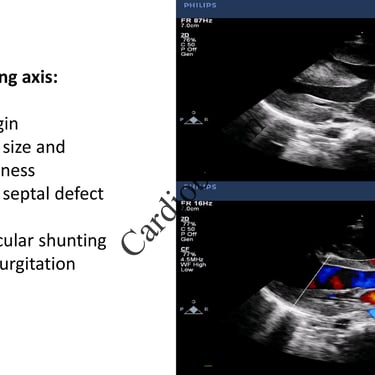

Truncus Arteriosus